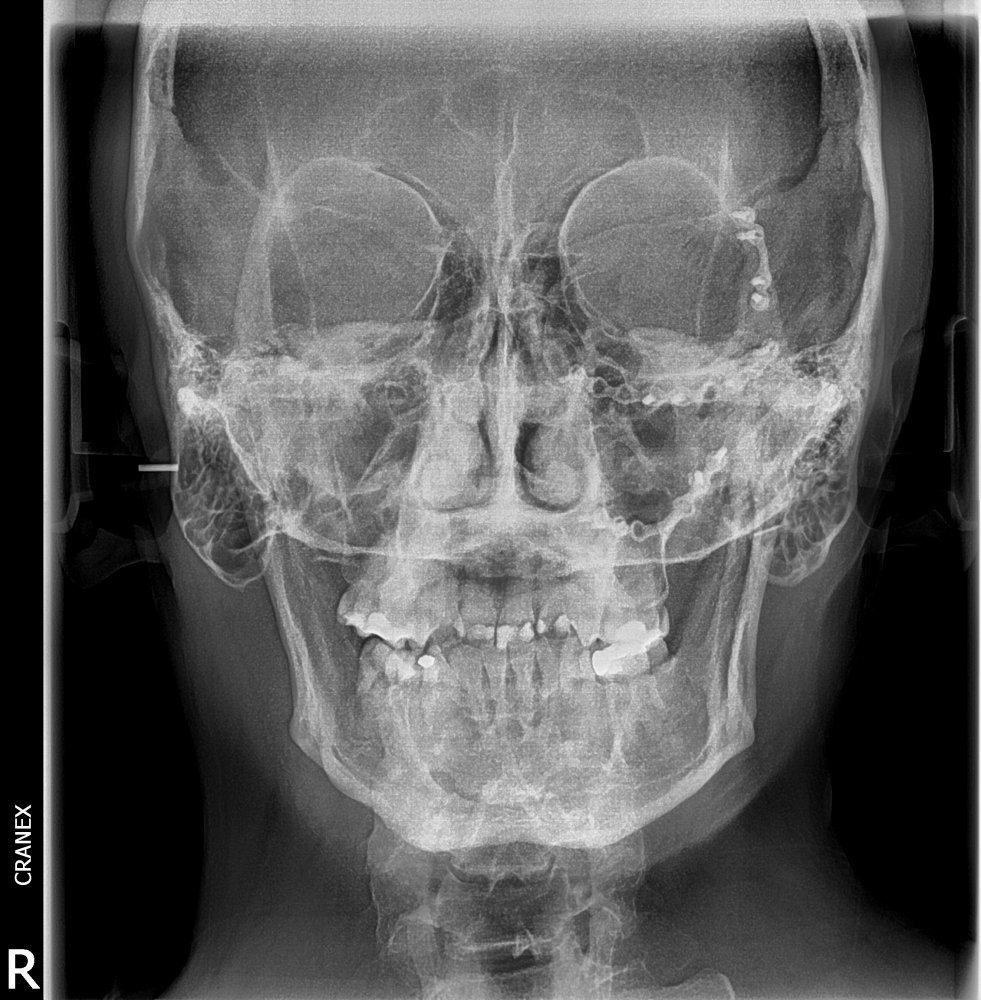

- RX. Frontal (Postero-anterior)